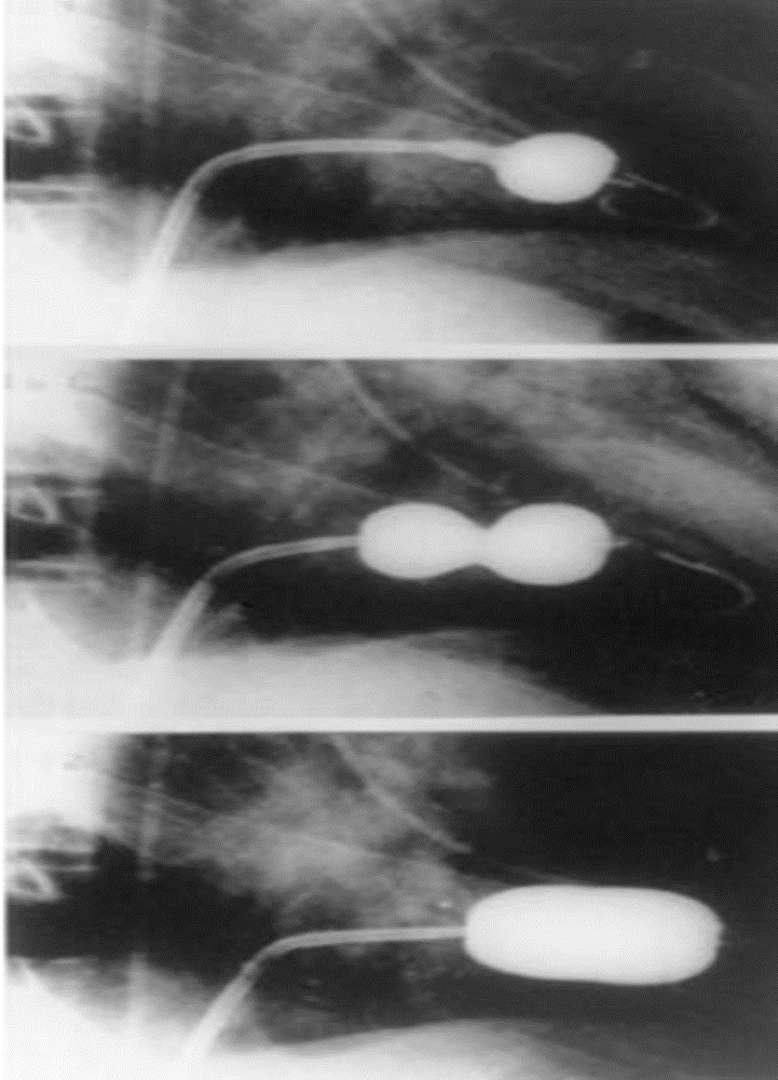

Percutaneous mitral valve balloon commissurotomy (PMBC)

Percutaneous mitral valve balloon commissurotomy (PMBC) [15]

- PMBC is the preferred intervention in most patients with severe MS.

- A balloon catheter is advanced percutaneously through the mitral valve and inflated to break open commissural stenosis and increase the mitral valve area. The Wilkins score is used to determine eligibility.